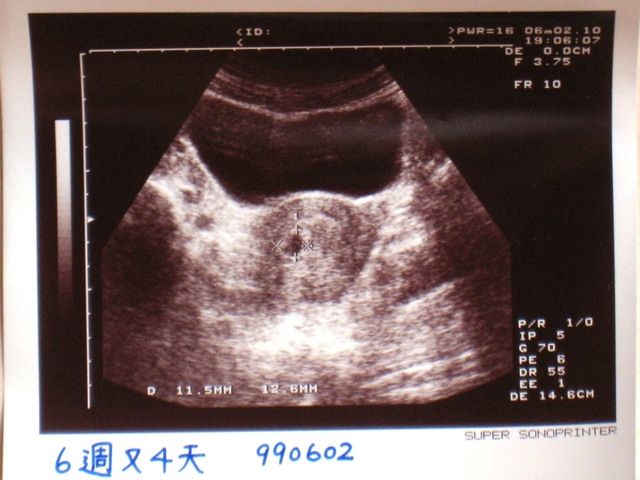

之後生我算的大小,好是6又4天

且等一下直接照一下腹部超音波看看的

生於停止手上的作,很心的指著幕上的一小黑宣布:

『就是胚胎啦!』

『恩!著床位置很好,不太下面;子厚度也,大小也正常。』

不生因今天不,所以看不到心跳

等拜,要我再回看的心跳

99.6.2,透超音波,和我的小初次面!:)